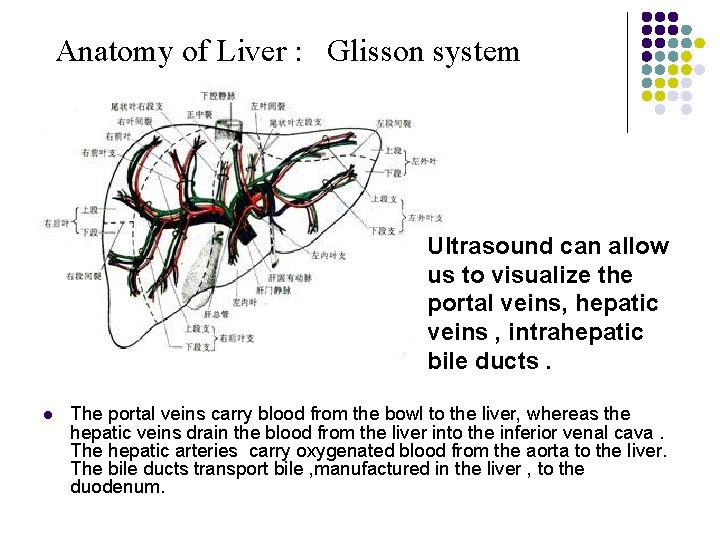

Anatomy of Liver : Glisson system Ultrasound can allow us to visualize the portal veins, hepatic veins , intrahepatic bile ducts. l The portal veins carry blood from the bowl to the liver, whereas the hepatic veins drain the blood from the liver into the inferior venal cava. The hepatic arteries carry oxygenated blood from the aorta to the liver. The bile ducts transport bile , manufactured in the liver , to the duodenum.